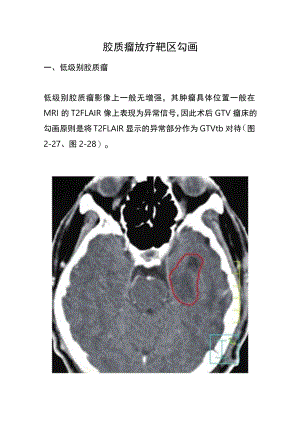

胶质瘤放疗靶区勾画一、低级别胶质瘤低级别胶质瘤影像上一般无增强,其肿瘤具体位置一般在MRI的T2FLAIR像上表现为异常信号,因此术后GTV瘤床的勾画原则是将T2FLAIR显示的异常部分作为GTVtb对待(图2-27、图2-28)o增强CT仅见左侧颗叶术后低密度区FLAIR显示的异常信号大于术腔图2-27口级星形细胞瘤术后GTVtb(红线)以包括FLAIR显示的异常信号为原则图2-28少突胶质瘤(II级)术后GTVtb(红线)的勾画以T2FLAIR显示的异常信号为原则,黄线为外扩1.5cm的CTV而CTv一般根据分化程度而有所不同:病理分化为I级者,CTV=GTV+1cm(即在GTV基础上外放1.0cm)o病理分化为II级者,CTV=GTV+12cm(即在GTV基础上外放12cm)o二、恶性胶质瘤恶性胶质瘤,即高级别胶质瘤印、IV级者,GTV.CTV的设计目前仍有争议,争议的主要焦点如下。(-)GTVtb的设计术后往往在瘤床周围会有强化带的存在,多数主张以此为GTVtb,并以此外扩作为CTV的依据,但也有学者将强化带周围的T2FLAR异常信号作为GTVtb对律图2-29)。Tl强化病灶作为GTVtbT2FLAIR异常信号作为GTVtb图2-29GTVtb的两种勾画方法(二)CTV的设计CTV的靶区设计主要涉及下面两个问题。1.CTV是否需要包括瘤周的水肿区?RTOG推荐CTV1需包括全部瘤周水肿及水肿区外2cm区域,给予46Gy,缩野后CTV2需在大体肿瘤靶区(GTV)外扩2cm,剂量增至60GyoEORTC推荐的CTV设计并不强调一定要包括所有瘤周水肿区而是以术后瘤床强化带外放23cm为逆图2-30)o图2-30胶质母细胞瘤术后GTV包括增强MRI所显示的范围,外放3cm并适当修正为CTV欧洲EORTC(EuropeanOrganisationforResearchandTreatmentofCancer)和美国RTOG(RadiationTherapyOncologyGroup)的靶区勾画原则见表2-1o表2-1欧洲EORTC和美国RTOG胶质瘤的靶区勾画原则比较EORTCRTOGWHOIV级1个计划(60Gy30次)GTV术腔+MRITl强化组织CTVGTV+2cm2个计划:第一计划46Gy23次GTV-术腔+MRITl强化组织+T2或FLAIR像水肿区CTV=GTV+2cm第二计划l4Gy7次GTV=术腔+MRITl强化组织CTV=GTV+2.5cm(强化X域外放2.5cm)EORTCRTOGwhom级I个计划(59.4Gy33次)源自EORTC26O53Z22O54.CATNON试验.非Ipl9q缺失的Ill级胶质情GTV=术腔+MRiTl强化+T27LAJR像升常信号CTVGTV+1.52cm(解剖屏障处7-IOmm已够)2个计划EORTC2695H间变少突和少突班形细胞制)第一计划45Gy25次第二计划14.4Gy8次CTVI=术前T2异常+2cmCTV2=术后T2异常+Tl强化+Icm2个计划源自RTOG9402试验.间变少突和少突星形细胞瘤第计划50.4Gy28次GTV=T2或FLAIR像计常信号CTV术腔+MRiTl强化+T2FLAIR像异常信号+Icm第:计划9Gy5次GTV=术腔+MRITl强化组织CTV=GTV+1.5cm(强化区域外放1.5cm)WHOIl级源自EORTC22033-26033/CE5试验I个计划(50.4Gw28次)GTV=水腔+MRIT2/FLAIR像异常信号CTV=GTV+1-2cm源1RTOG9802试验I个计划(54Gy30次)GTV=T2或FLAIR像异常信号CTV=GTV+Icm2020美国国立综合癌症网络(NationalComprehensiveCancerNetworkzNCCN)指南推荐MRT1增强或T2FLAR异常信号为GTV外扩12cm形成WHoIn级胶质瘤的CTV,而外扩22.5cm形成GBM的CTVoCTV外扩35mm形成计划靶区(planningtargetvolume,PTV);而T2/FLAR显示的水肿区建议包括在第1计划CTV1第46Gy23次)第2计划增量区(Boost:14Gy7次)应仅仅包括残余肿瘤或术后瘤腔外扩2.0cm形成的CTV2o2.GTV到CTV外扩的原则CTV是在GTV基础上外放形成的,但绝不能是单纯几何学的外放,而是要考虑众多因素适当修整而形成合理的CTV设计。(1)颅骨作为屏障,CTV至颅骨内板即可。(2)大脑镰和小脑幕有一定的屏障作用,一般外放至大脑镰和小脑幕外时要及时修回至大脑镰或小脑幕,或最多包括大脑镰到对侧不超过5mm的距离即可。(3)胶质瘤容易沿白质纤维束浸润,因此瘤体邻近的白质纤维束应适当多包,而灰质区域适当少包。(4)月并版体是最大的白质纤维束,一侧大脑半球病变可通过月并版体到达对侧大脑半球,因此CTV毗邻月并脏体的部位要适当多包(图2-31)o胶质母细胞瘤通过月并肌体前部侵犯对侧胶质母细胞瘤通过骈脏体后部侵犯对侧图2-31胶质母细胞瘤侵犯对侧的途径(5)一侧大脑半球病变可通过大脑脚而侵犯脑干,如大脑脚受侵,则其邻近的脑干不能过多保护。(6)胶质母细胞瘤常见扩散途径是通过月并脏体、内囊、穹窿、前联合及视辐射直接蔓延。中国医学科学院肿瘤医院设计原则基本采纳EORTC标准,并根据具体情况做适当的个体化处理。GTVtb:原则上讲,GTVtb包括术后强化带及T2FLAIR异常部分(如术后有明确的肿瘤残存,也可将残存肿瘤勾画为GTVp而给予较高的剂量)。但在临床处理上,应根据具体情况个体化处理:如果病灶不大,则术后增强的区域及T2FLAIR像异常信号均包括在GTVtb(图2-32);增强MRl显示的瘤床T2FLAIR显示强化病灶后方的异常信号区图2-32胶质母细胞瘤术后GTVtb包括增强MRI÷T2FLAIR异常信号所显示的范围但如果病灶较大如遵照包括全部FLAlR像异常信号作为GTVtb对待的原则,则相应的CTV会明显扩大(图2-33)。图2-33患者GTVtb以左图为准,仅包括强化的病变范围。图2-33胶质母细胞瘤术后GTV的勾画,以增强MRI所显示的瘤体为原则CTV:在GTVtb基础上外扩23cm并适当修改形成。病理分化为HI级者,CTV=GTV+1.52.0cm0病理分化为IV级者,CTV=GTV+2.03.0cm,现多主张外放距离多不超过2cm0当然也可设计为2个CTV,如CTV1在GTV外放1.5cm.CTV2在GTV外放2.5cm,可以给予不同的分次剂量及总剂量。()PTV的设计PTV=CTV÷35mm,靶区的剂量按照相关的PTV给量。(四)危及器官的限量在靶区设计的同时,对靶区周围的重要器官如脑干、脊髓、角膜、晶体、视神经等进行勾画,并限定安全剂量。当采用分次剂量为182.0Gy的照射时z各重要器官的剂量应限制在:全脑50Gy,部分脑60Gy;脑干54Gy;脊髓45Gy;视交叉5054Gy;视网膜45Gy;晶体9Gy;内耳30Gy;月兑发2030Gy;泪腺30Gy(暂时性),60Gy(永久性)。(五)剂量分次剂量一般为1.82.0Gy建议单次剂量不超过2Gy,但对于明显残存肿瘤、且位于非重要功能区时,允许残存肿瘤分次剂量适当提高至2.12.2Gyo总剂量与分级有关。一般而言,低度恶性者总剂量50.4-56Gy,高度恶性者GTV为6066Gy,CTV1为60Gy,CTV2为54Gyo